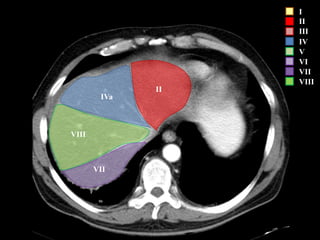

I – Entre cava y porta

II – el más superior de los izquierdos

III – Por debajo del II

IV – por delante de la vesícula

V – por detrás de la vesícula

VI – relación con riñón derecho

VII – el más posterior de los segmentos superiores

VIII – domo hepático

Las claves de la segm. Hepática